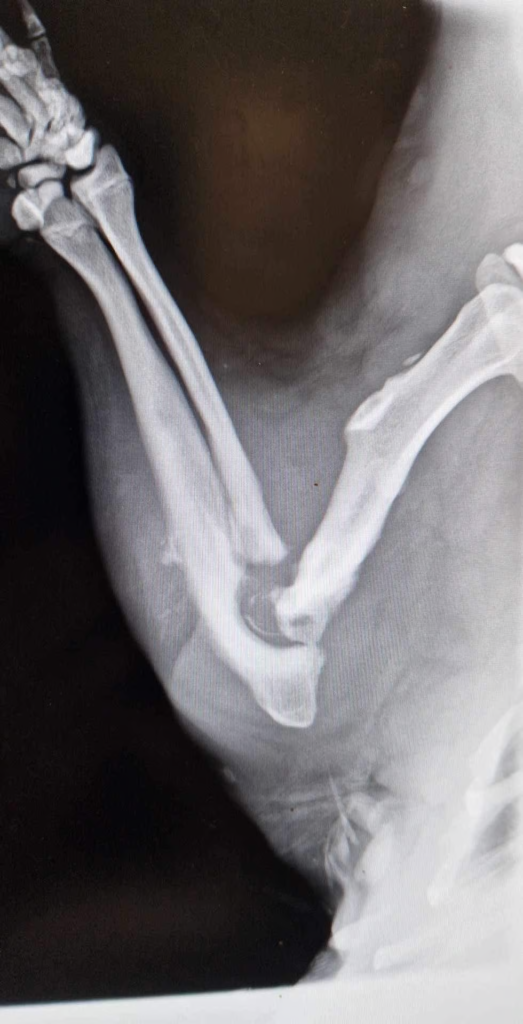

Выяснилось, что бобёр в тяжелом состоянии, с несколькими глубокими, гнойными ранами. Ему также придётся ампутировать конечность, потому что, вероятно, у него рак. На самом деле это не совсем бобр, а самка бобра.